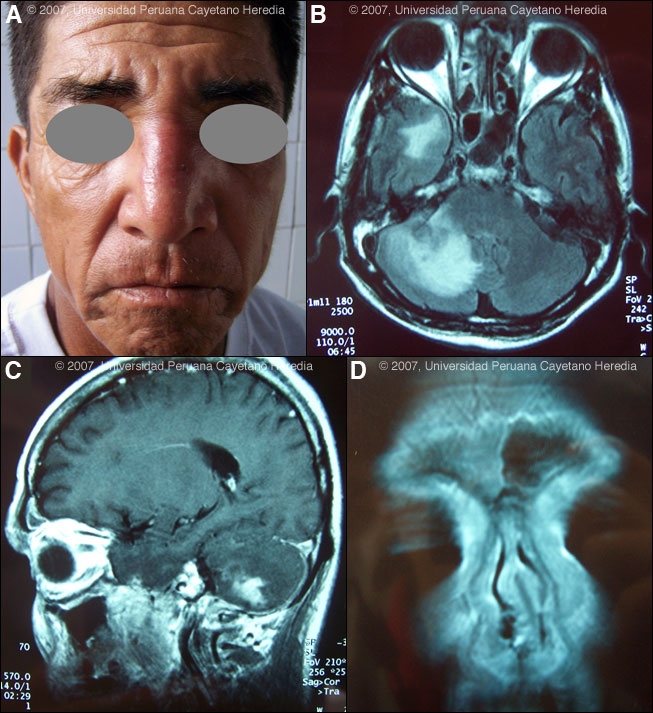

History: 57-yo male who noted a papular and erythematous lesion on the nose fourth months ago that was not associated with pain, itching or constitutional symptoms. Two months ago he noticed a single episode of epistaxis, and progressive enlargement of the lesion with infiltration of the nasal mucosa of the left side that produced nasal obstruction and anosmia. Two weeks before admission the patient noticed severe constant headache and presented for further evaluation. Itraconzale (100 mg/d) and co-trimoxazole were started 2 months earlier at another hospital with minor improvement of the skin lesion. He has been previously healthy with no history of sinus, nasal, or neurologic problems. Epidemiology: The patient is a farmer from Sechura, Piura in the coastal desert 900 km north of Lima. He raises cattle, cats, and dogs, and he fishes and collects bamboo in local rivers and ponds. No known exposures to TB, ill people, or ill animals. Physical Examination: Afebrile. Infiltrative and erythematous lesion on the nose [Image A]. Nasal mucosa with an edematous and erythematous mucosa and deviation of the septum to the left. The rest of the exam was normal including a complete neurologic exam. Laboratory Tests: Hematocrit 40%, WBC 14,000 (78% neutrophils, no eosinophils), platelets 480,000. Normal liver function and chemistry. Cerebrospinal fluid with 364 white cells, 62% polymorphonuclear cells, 38 mononuclears; glucose 45 mg/dl (normal), proteins 95 mg/dl (high); gram stain negative, India ink negative and bacterial culture negative. HIV negative. MRI shows multiple enhancing lesions located in the cerebral parenchyma, cerebellum and brainstem [Images B and C]. Involvement of the right frontal sinus and extensive involvement of the nasal mucosa of both sides but specially the left side is also observed [Image D]. A biopsy was obtained.

![]() Discussion: A skin biopsy of the lesion over the nose showed a dense immflamatory infiltrate of the dermis composed of lymphocytes, plasma cells and multinucleated cells with granulomas. There are multiple trophozoites of a free-living amoeba [Image E, ovals]. Note the small nucleus eccentrically located and the vacuolated cytoplasm [Image E, magnification]. Definitive identification of Balamuthia requires culture or specific immunostaining, and successful use of PCR has been reported. However, other species of free-living amoeba are not known to occur in Perú. Around 100 cases of Balamuthia mandrillaris have been reported since the organism’s initial description in 1990 [Clin Infect Dis. 1997 Dec;25(6):1354-8]. Half or so have been in the USA, mostly in immunocompromised patients. Cases have also occurred in Canada, Mexico, Australia, Argentina, Brazil, Mexico, Thailand, Japan, the Czech Republic, Portugal, and England. A significant number of the published cases from the United States have occurred in persons of Hispanic ethnicity. Additional reports have come from Canada, Japan, Australia, Thailand, and Eastern Europe, as well as from throughout Latin America. We have seen over 50 cases at our institution and, like most Latin American cases, the patient is not immunocompromised. Unlike Acanthamoeba and Naegleria species, which are more familiar to clinicians and known to occur in brackish ponds and creeks, an ecologic niche in nature has not been definitively found for Balamuthia. Our patients have come from throughout rural areas of Perú, and usually, but not always, have a history of swimming in potentially contaminated fresh water. Entry of water into the nasal mucosa and the olfactory nerve endings is thought to occur with Acanthamoeba and Naegleria. Naegleria infection causes an acute necrotizing and suppurative meningoencephalitis, an aggressive disease that is generally fatal in days. Acanthamoeba cause a sub-acute granulomatis encephalitis with a more prolonged but ultimately fatal course. Occasionally patients with Acanthamoeba have a skin lesion usually described as a chronic ulcer. Acanthamoeba, unlike Balamuthia, has been associated also with amoebic keratitis, a painful sight-threatening disease of the eye. In Balamuthia infection the disease may follow a prolonged course, but most frequently has a fatal outcome. Almost all cases have an initial skin lesion, and this lesion precedes the inevitable CNS disease (granulomatous amebic encephalitis) by weeks or months. Patients have ranged from 5 to 65 years of age with 50% under age 15. The typical skin lesion is a single painless plaque up to several centimeters in diameter; a few patients have had 2 to 3 lesions. Color may be skin tone, dark red, or slightly violaceous. Sensation is preserved. Location is usually on the central face but occasionally on trunk or extremities. For facial lesions the differential diagnosis may include tuberculosis, mucocutaneous leishmaniasis, leprosy, sporotrichosis, paracoccidioidomycosis, rhinoscleroma, or mucormycosis. Sarcoid, discoid lupus, and Wegener's can also be considered. Histologically, granulomatous inflammation with lymphocytes, histiocytes, plasma cells, as well as giant cells, is characteristic. Amoebic trophozoites are often scanty and multiple sections need to be examined. Some foci of vasculitis may be present. CNS involvement manifests with heachache, photophobia, seizures that progress to lethargy, sensorimotor deficit, coma and death. The CNS lesion is a progressive hemorrhagic necrosis with large numbers of amoebic trophozoites and cysts invading vascular sub-adventitial areas of arteries, veins, and capillaries, leading to perivasculitis and cerebral infarcts [Hum Pathol. 1999 Mar;30(3):269-73]. No therapy has been shown to be highly effective in curing Balamuthia infection. With IV amphotericin B or pentamidine, an initial and apparently favorable response or disappearance of cutaneous lesions still does not halt the eventual appearance of CNS disease. Similarly, in our hands, multi-drug combination therapy with agents such as albendazole, itraconazole, or fluconazole have still resulted in eventual appearance or progression of CNS disease. In our hands there have been 4 survivors out of 10 patients treated with aggressive combination therapy followed by 6-12 months of albendazole maintenance. One or two case reports from other centers have reported success with regimens that have also included sulfadiazine, macrolides and phenothiazines. The current patient was started on fluconazole 400 mg/d, albendazole (800 mg/d) and amphotericin B 1.0 mg/kg/d. He developed gait abnormalities and increased intracranial pressure on Day 3 of hospitalization and died 1 week later.